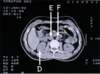

Benævn de markerede strukturer (A og B) på de viste scanninger.

A: pyramis renalis (nyrepyramide),

B: v. renalis sinistra